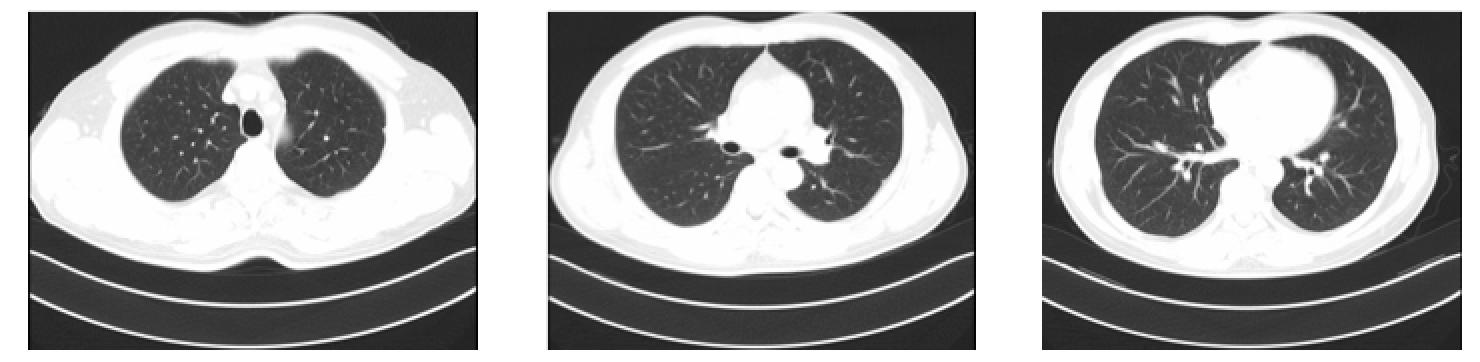

胸部CT

右肺中叶及左肺上叶尖后段少许感染。

4、右肺中叶及左肺上叶尖后段少许感染

右肺中叶及左肺上叶尖后段纤维条索影。

左肺下叶外基底段小结节影:炎性结节?请随访。

肺中叶及左肺上叶少许纤维条索。

上述表现比较2017-04-26CT无明显变化。